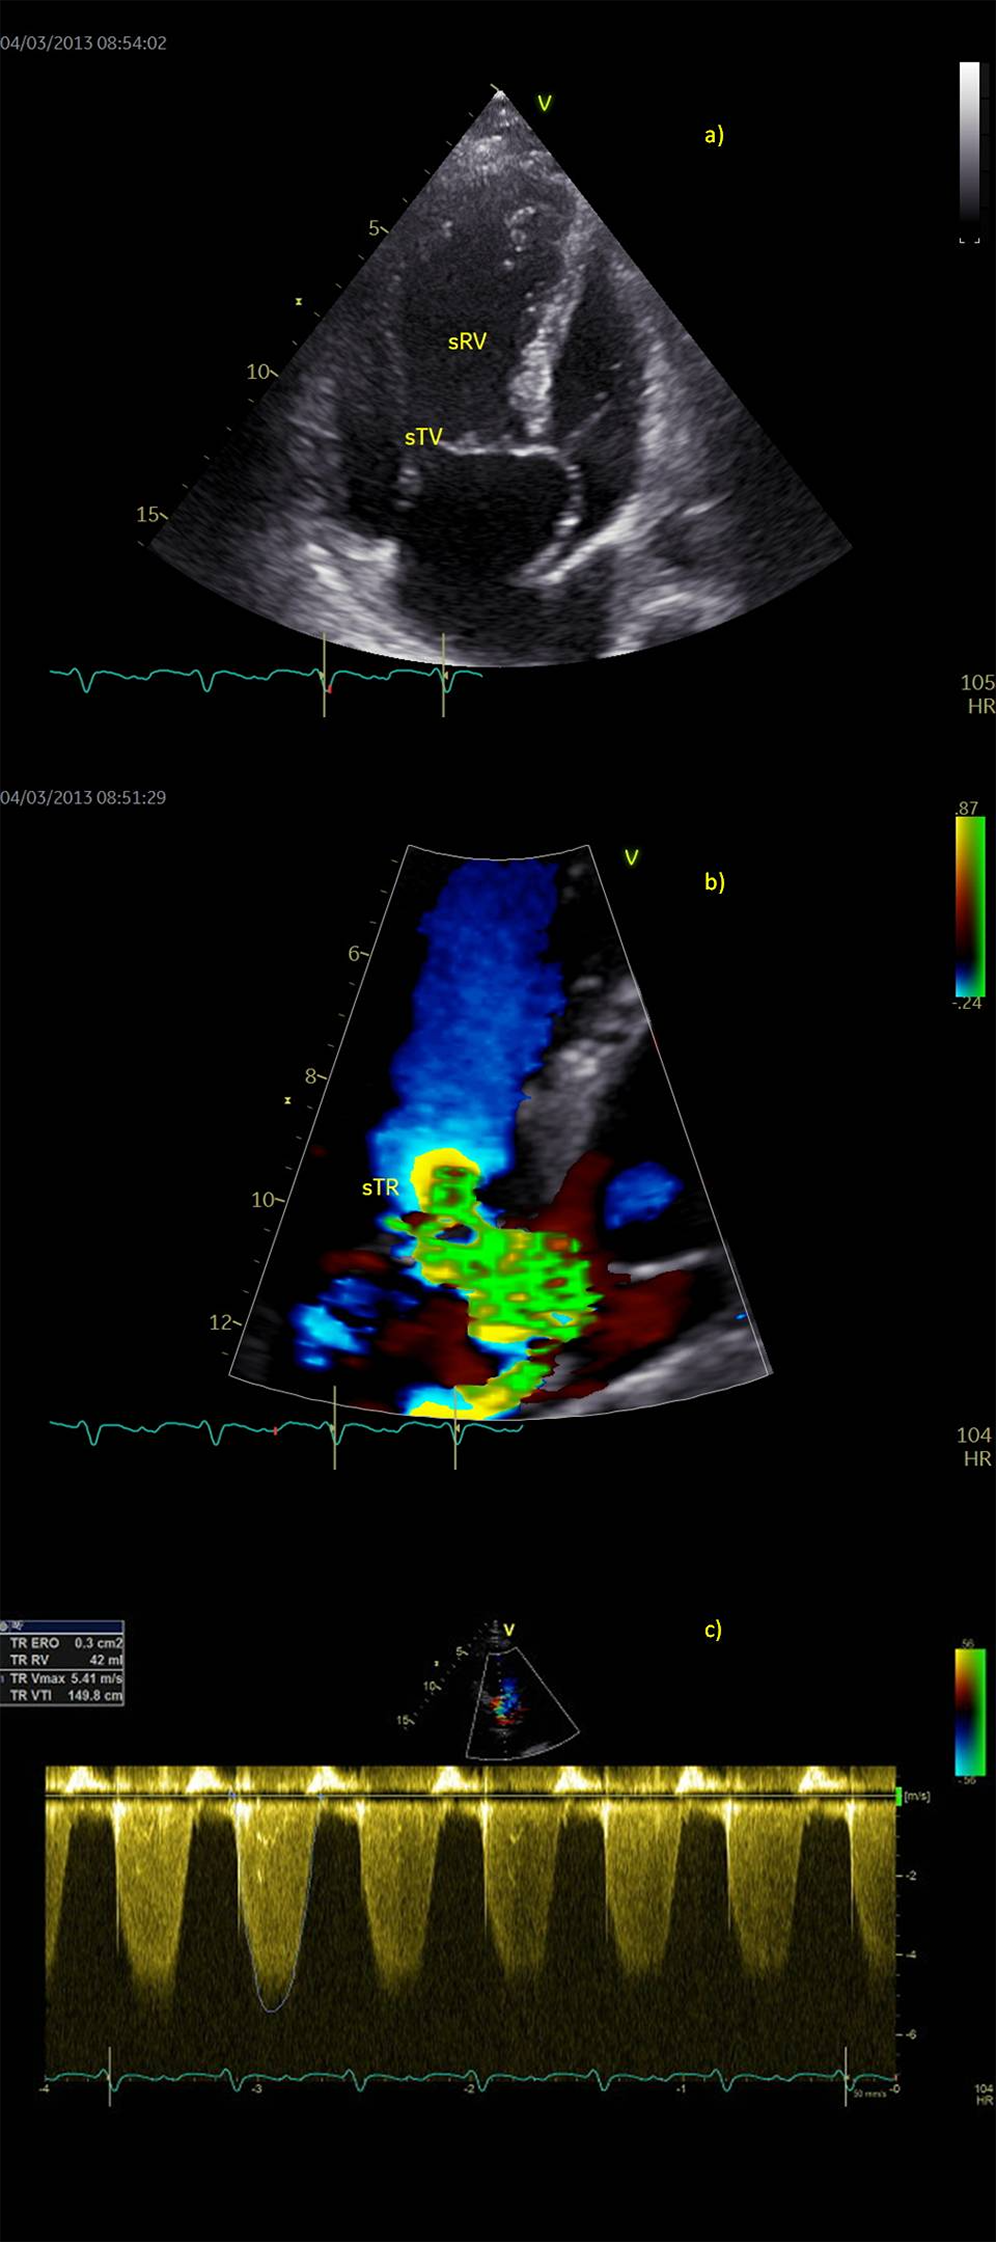

We present a case of a 33-year-old female patient (written informed consent was signed by the patient) with TGA, treated with septostomy by Rashkind a few days after her birth and by the Senning procedure at the age of nine months. She was presented in our clinic with palpitations and dyspnea in 2011, at the age of 26. At that moment she was hemodynamically stabile, tachycardic 106/min with a systolic heart murmur (3/6) and no clinical signs of congestion. Auscultation of the lung revealed no signs of congestion and no peripheral edema was present. Auscultation of the lung revealed no signs of congestion and no peripheral edema was present. Monitoring electrocardiogram (ECG) showed a continuous atrial undulation (UA) and wide QRS, so antiarrhythmic therapy with bisoprolol and amiodarone was started. Beside the arrhythmia, echocardiographic examination (ECHO) revealed a dilated sRV with end-diastolic volume (EDV RV) of 220 ml (126 ml/m2), moderate sTR due to combined functional regurgitation with primary valve lesion-prolapse of posterior leaflet, and reduced EF of sRV 42%. Due to drug- and electrocardioversion resistant arrhythmia a successful radiofrequency ablation of the re-entry tachycardia was performed in December 2012. During the next four months of follow up the patient was clinically compensated, in New York Heart Association (NYHA) I functional status, with no change in effort tolerance. Control ECG monitoring in March 2013 revealed recurrence of UA while control ECHO verified a worsening of sTR (regurgitation volume > 50% of the stroke volume) to severe regurgitation and moderate reduction of sRV systolic function. Pulmonary artery pressure was not elevated. Due to a resistant and long-lasting UA, systolic function of sRV progressively declined implicating a component of tachycardia induced cardiomyopathy, followed by an increased regurgitation volume of sTR (Figs. 1a–1c). Gadolinium scan (magnetic resonance) of sRV showed a dilated systemic right atrium, dilated and hypertrophied sRV (EDV 161 ml, 92 ml/m2, end-systolic volume (ESV) 83 ml, stroke volume (SV) 78 ml, EF 48%), thin left ventricle (LV) walls (EDV 76 ml, ESV 30 ml, SV 46 ml, EF 60%), no regional contractility abnormalities and no signs of replacement fibrosis. Coronary stenosis was ruled out by coronary angiography. Native ECG showed RBBB with QRS width 140 ms. The patient was scheduled for sTV replacement and AV node ablation to be followed by implantation of pacemaker. During the surgery, a biological TV prothesis (pTV) (Edwards Lifesciences C-E Perimount Magma Mitral 33 mm) was implanted and AV node ablation was performed. In order to prevent mechanical iatrogenic dysynchrony of permanent pacing, a CRT with biventricular pacing was implanted during surgery, placing epicardial bipolar leads (Medtronic Model 4968, atrial lead on sRV and ventricular lead on LV in DVIR pacing mode, with AV delay of 30 ms). The optimization of lead placement was guided using transesophageal echocardiography in order to find the most favorable stimulation sites on the right and left ventricular walls that would achieve the most synchronous sRV contraction. An echocardiographic control (April 2013) revealed a positive remodelling of sRV based on reduction of EDV RV to 60 ml, an increase in EF RV 60% and synchronous myocardial contractions (Figs. 2a–2c) and QRS 130 ms. The CRT memory follow up data showed no arrhythmias, so betablockers could be discontinued and the risks during pregnancy decreased to an acceptable level. Nineteen months later an ovarium dermoid cyst removal and correction of septate uterus was performed. Three years after the surgery, the patient was in NYHA Class I, with normal sRV size and function and synchronous myocardial contractions (Fig. 2). The underlying atrial rhythm was UA. The patient was diagnosed with hereditary thrombophilia. Despite increased risk of cardiovascular events, our patient had a strong motivation and an increasing wish to become a mother that we approved. After several attempts of unsuccessful in vitro fertilization procedures, a twin pregnancy was achieved. In the 30th week of gestation, in July 2017, no clinical signs of heart failure (HF) were present but ECHO revealed a slight dilatation and worsening od EF of sRV and sTR (EDV 140 ml, ESV 70 ml, EF 45%). Despite the suggested restriction of physical exertion and bed rest in the following gestational weeks, an excessive volume overload and further dilatation of sRV were noticed.

Figure 1: Preoperative echocardiography in a patient with failing systemic right ventricle (sRV), a) Apical four-chamber view, b) Color flow of severe tricuspid regurgitation (sTR), PISA 10 mm, regurgitant volume 42 ml. c) Holosystolic and dense continuous Doppler trace of tricuspid regurgitation flow (sTR VTI 150 cm)